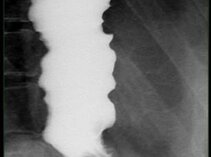

Die Durchleuchtung wird meist zur Darstellung der Gestalt und der Funktion des Magen-Darm-Traktes eingesetzt. Dazu verabreichen wir Jod- oder Barium-haltiges Kontrastmittel unter Röntgenkontrolle.

Heute steht die Funktion der Hohlorgane im Vordergrund: Darstellung des Schluckaktes, Durchgängigkeit von operativen Verbindungen z.B. zwischen Speiseröhre und Dünndarm sind Beispiele dafür.

Ösophagus-Untersuchung mit Barium (ggf. incl. Videoskopie)

Beispielbilder